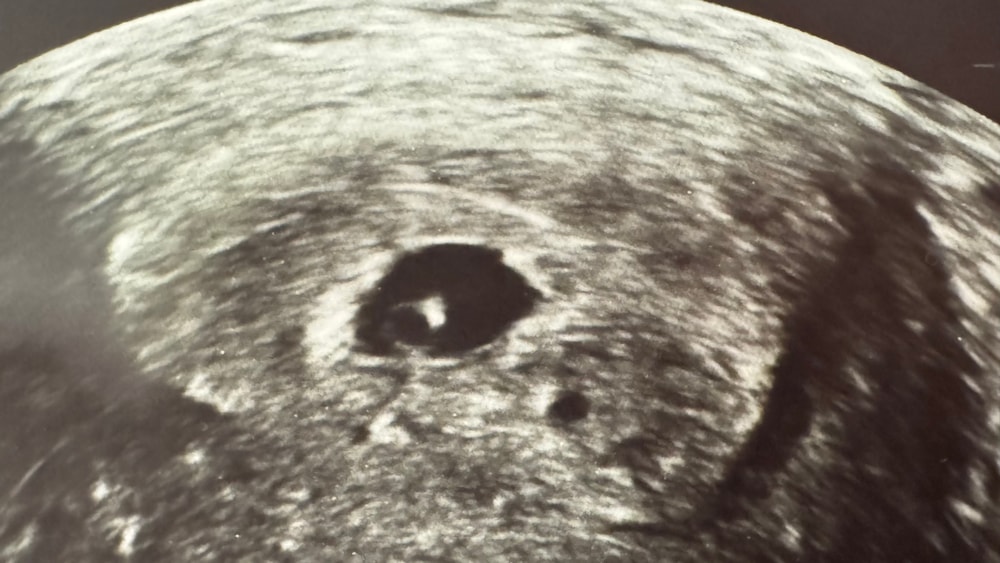

1ый криоперенос_1я беременность_1ое УЗИ 21дпп

А для меня оно совсем особенное, ведь сегодня у меня было первое УЗИ, т.е. знакомство с моим малышом.

А самое главное, что есть эмбриончик с сербцебиением (пульсация) 🙏

Ре сказала, что на таком сроке, не часто можно увидеть эмбриончика и увидеть пульсацию. Но мой малыш-настоящий молодец! 🥰